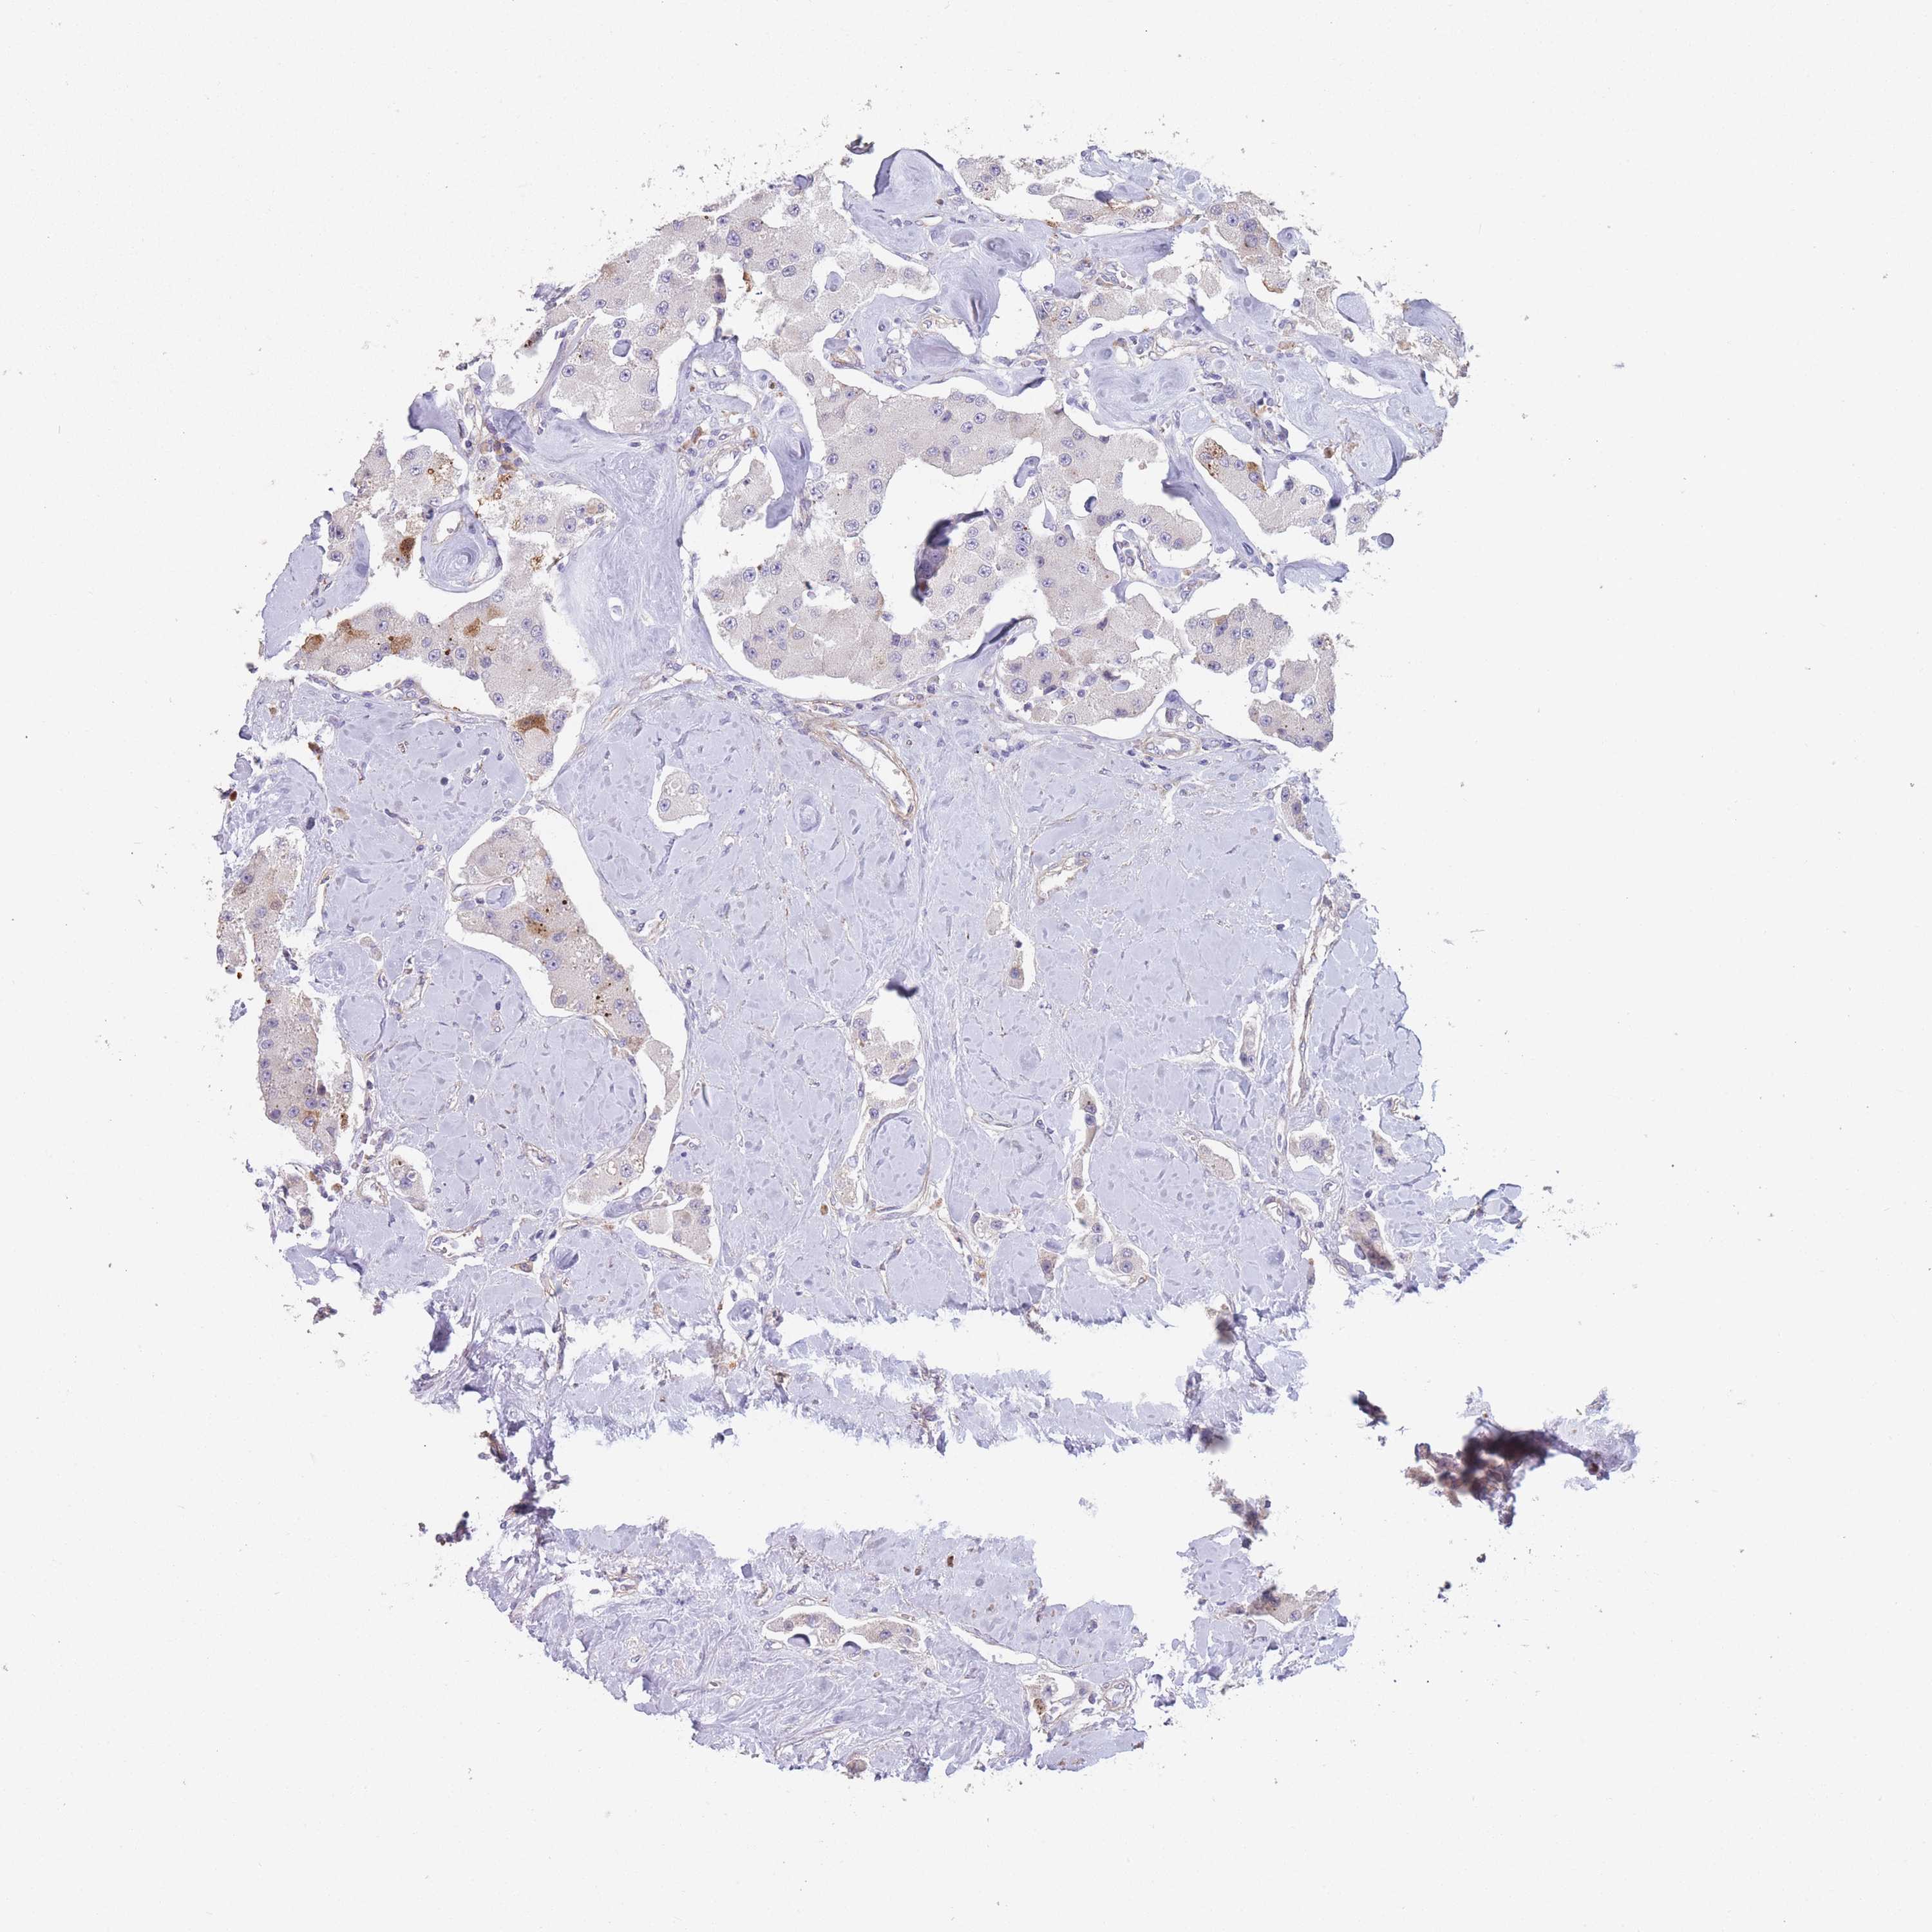

Neuroendocrine tumors

Human pathology

Carcinoid